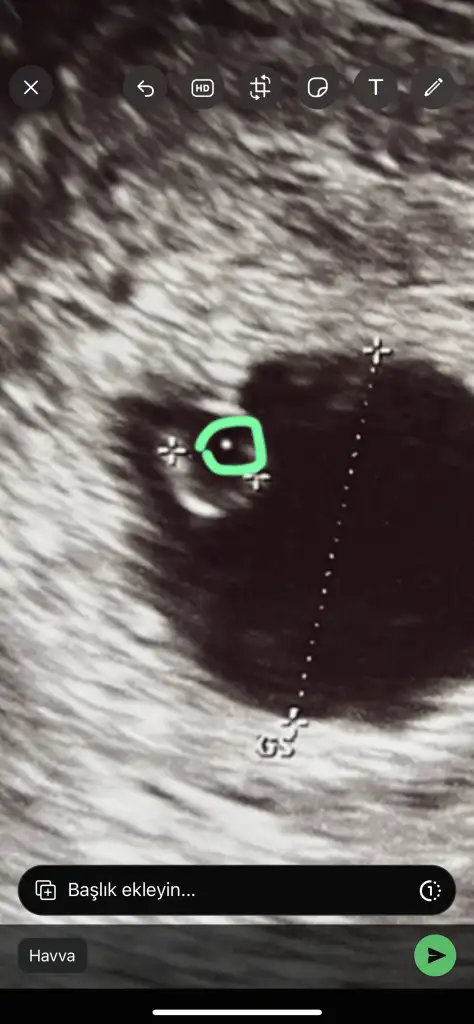

Hem suan sende bebek gorunuyor kalp atisinimi duyamiyorsunuz bence bekle bebek gorunuyor

Doktor bebeğin bu olduğunu söyledi ve maalesef gelişmemiş dedi yarına 8+3 oluyor gelişmesi durmuş tek tas şeklinde olması gerekiyormuş yarın başka bir doktora gideceğim ama görüntü aynı şekil olursa ki büyük ihtimal öyle olacak çarşambaya kürtaj olacağım 😔